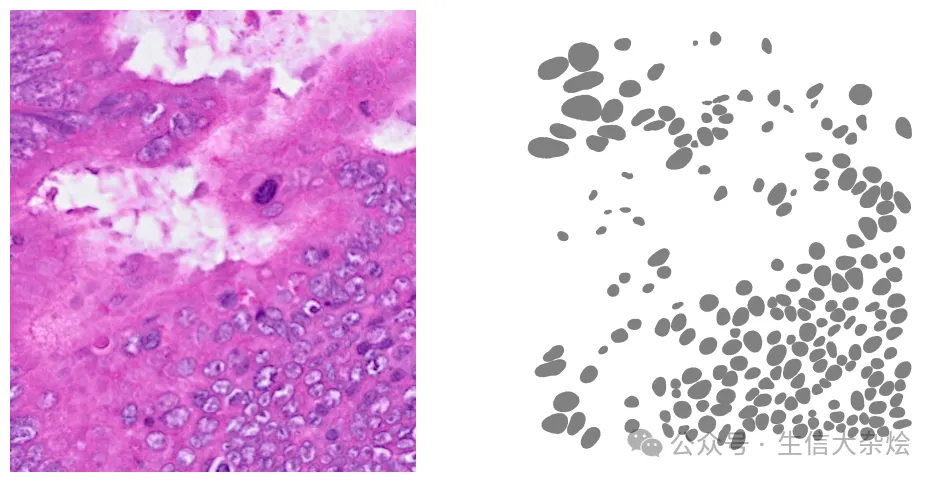

# Convert polys to geometriesgeometries = []# Iterate over each nuclei detected in the imagefor nuclei in range(len(polys['coord'])):    # Extract the x and y coordinates    coords = [(y, x) for x, y in zip(polys['coord'][nuclei][0], polys['coord'][nuclei][1])]    # Add the polygon to the list of geometries    geometries.append(Polygon(coords))# Create the geodataframegdf = gpd.GeoDataFrame(geometry=geometries)# Add a unique ID columngdf['id'] = [f"ID_{i+1}" for i, _ in enumerate(gdf.index)]gdf.head()x_min = 1000x_max = 1512y_min = 400y_max = 984bbox = (x_min,y_min,x_max,y_max)cropped_img = img[bbox[1]:bbox[3], bbox[0]:bbox[2],:] # Plot optionsfig, axes = plt.subplots(1, 2, figsize=(12, 6))# Plot the cropped imageaxes[0].imshow(cropped_img, cmap='gray', origin='lower')axes[0].axis('off')trim = 10bbox_polygon = Polygon([(bbox[0]+trim, bbox[1]+trim),                         (bbox[2]-trim, bbox[1]+trim),                          (bbox[2]-trim, bbox[3]-trim),                           (bbox[0]+trim, bbox[3]-trim)])# Filter for polygons in the boxintersects_bbox = gdf['geometry'].intersects(bbox_polygon)filtered_gdf = gdf[intersects_bbox]filtered_gdf.plot(cmap=ListedColormap(['grey']), ax=axes[1])axes[1].axis('off')plt.show()

图片